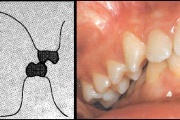

kahepoolse lõhega lapse hambumus

Valehambumus

Hammaste asendianomaaliad on tingitud tavaliselt arenguhäirest.